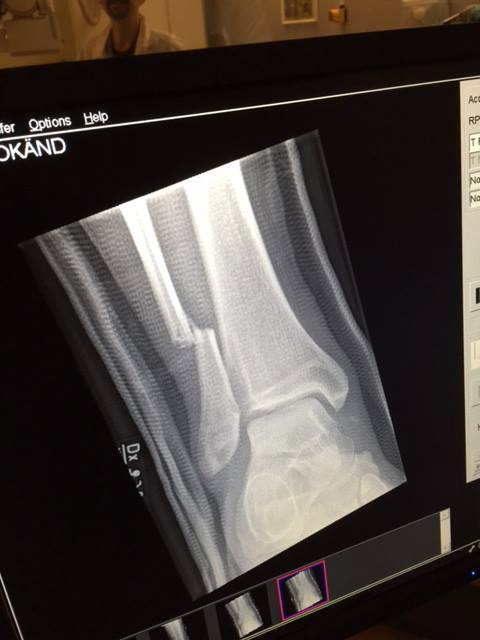

Zilele trecute, solistul Dave Grohl a căzut de pe scenă la un concert susţinut în Suedia, fracturându-şi piciorul. Spre bucuria fanilor, artistul şi-a continuat recitalul în ciuda durerilor.